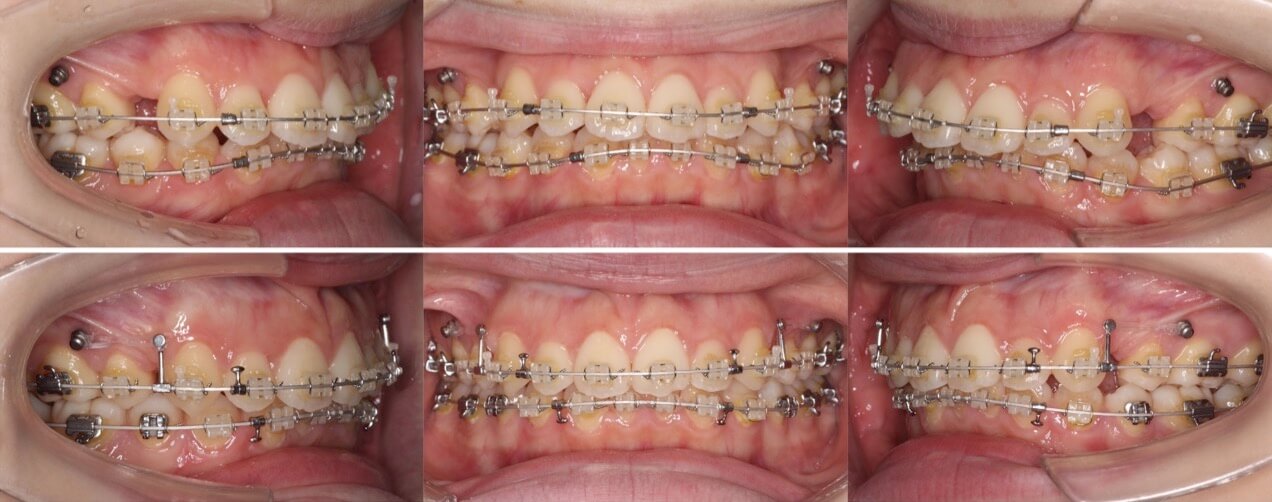

30代女性・先天性欠損4歯・5番欠損

症状:上下第二小臼歯先天性欠如・乳歯晩期残存・上下顎前突

治療方針:抜歯空隙閉鎖

治療装置:唇側矯正装置

固定源:下顎圧下アーチ

抜歯:上下乳臼歯(計4本)

治療期間:2年10か月

リテーナー:上下プレートタイプ+下フィックスタイプ

治療費用:964,000(税込)

代表的副作用:痛み・治療後の後戻り・歯根吸収・歯髄壊死・歯肉退縮

上下とも前から数えて5番目の歯が先天的欠損しているケースです。もともと口元が前方に突出している傾向にあったため、残存している乳歯を抜歯して前歯を後方に引っ込める治療を行いました。

乳臼歯は本来あるべき永久歯よりサイズが大きい傾向にあり、抜歯後の空隙閉鎖には通常より時間がかかります。下のワイヤーを2重にして少し強めの力をかけて治療期間の短縮を計画したのですが3年弱かかりました。

奥歯の先欠歯の抜歯矯正治療は、一般的な小臼歯抜歯矯正と比較して治療期間がかかる傾向になります。